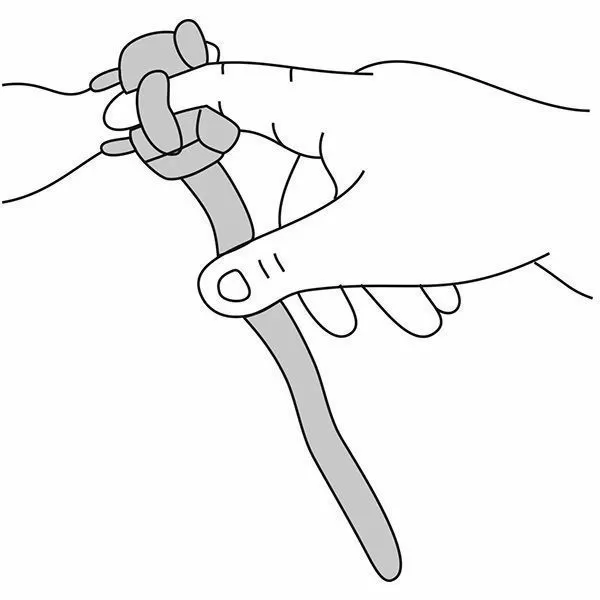

Почему может врать пульсоксиметр?

Причин, по которым пульсоксиметр может проводить измерения неверно, бывает несколько:

- у вас холодные руки. Согрейте их перед измерением;

- вы не до конца поместили палец внутрь прибора или измерению мешает длинный ноготь. Толстый слой гель-лака тоже может быть препятствием;

- вы долго находились в медицинской маске. Снимите ее, подышите глубоко и после этого делайте замер.